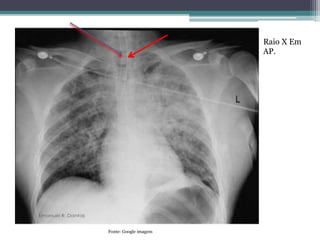

Raio X Em

AP.